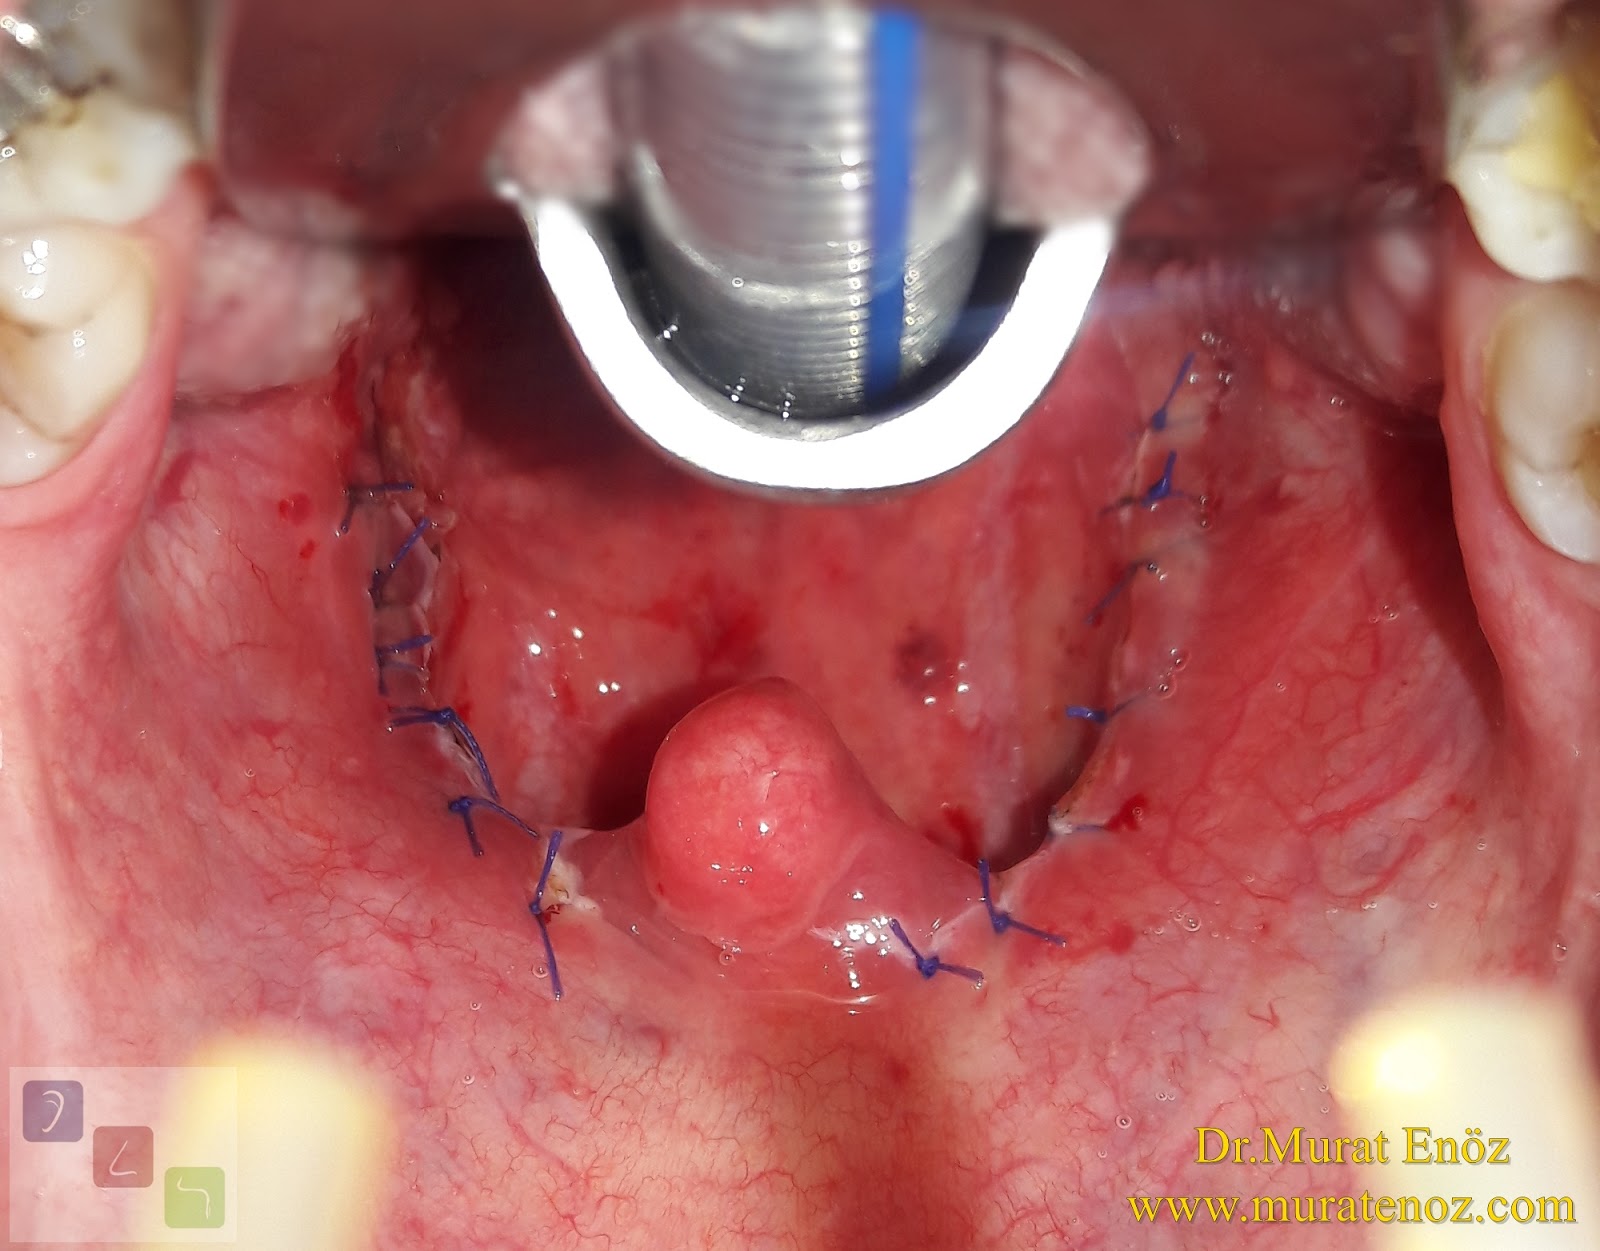

Thermal Welding Sistemi Ile Bademcik Ameliyati Ve Klasik Geniz Eti Ameliyati Oncesi Sonrasi Fotograflari

Thermal Welding Ile Agrisiz Kanamasiz Bademcik Ameliyati

Kismi Parsiyel Tonsillektomi Tonsillotomi Ve Tam Bademcik Ameliyati